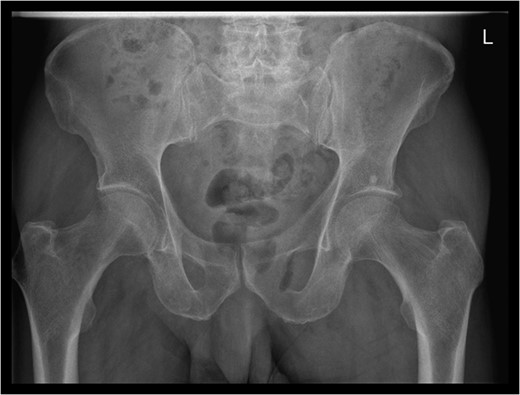

A rare complication of diverticular disease is the formation of fistulas, most commonly either colo-vesical or colo-vaginal. We present the unusual case of a perforated sigmoid diverticulum forming a colo-gluteal fistula and presenting initially as a gluteal abscess in an otherwise asymptomatic patient. After drainage of the gluteal abscess, the patient re-presented with faecal loss from the abscess drainage site. Imaging revealed fistulous communication between the sigmoid and the left obturator internus muscle, tracking to the gluteus maximus with associated abscess and cutaneous communication to the site of previous drainage. The patient underwent an emergency Hartmann's procedure with lay open/abscess drainage of the gluteal cavity. Post-operatively the patient experienced continuing discharge from the gluteal fistula despite repeated drainage and debridement causing considerable morbidity, inconvenience and misery. Clinicians should maintain a high index of suspicion when presented with a gluteal abscess and should consider the possibility of an intra-abdominal source.

A 67-year-old male was admitted to our acute unit with a 1-week history of a tender swelling over his left buttock/peri-anal margin. A course of oral antibiotics prescribed by his general practitioner had made no difference to his symptoms. He complained of severe pain in the left buttock associated with feverish symptoms. With hindsight, the pelvic/buttock pain seemed excessive compared with the outward appearance of the buttock swelling. He denied abdominal pain or alteration in bowel habit. His past medical history was significant for hypertension, atrial fibrillation, multiple previous myocardial infarctions and insertion of coronary stents. There was no past history of abdominal pathology.

Examination revealed a 2 cm area of tender erythema and induration over the left buttock/peri-anal region. There was also some bony tenderness noted on palpation of the left hip. Rectal examination was unremarkable.

An emergency Hartmann's procedure was performed under general anaesthetic through a lower midline incision as well as lay open of the perineal fistula. On opening the abdomen, a perforated diverticulum was identified extending into the left lateral pelvic wall. A standard Hartmann's procedure was performed, with sigmoid colectomy, division of rectum at recto-sigmoid junction and a tension-free stoma formed in left hypochondrium. The left buttock abscess cavity extended by a further 2–3 in. and the cavity then packed.